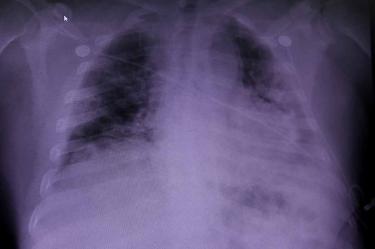

El coronavirus podría causar anomalías pulmonares que pueden ser detectadas más de tres meses después de que los pacientes se infectan, reveló una investigación.

Un estudio realizado en la Universidad de Oxford a 10 pacientes recurrió a una técnica de escaneo novedosa para identificar daños no detectados por exámenes convencionales, informa la cadena británica BBC.

Por medio de gas xenón se pudieron obtener imágenes del daño pulmonar durante las resonancias magnéticas.

A través de esta técnica, los pacientes inhalan el gas durante una exploración por imágenes de resonancia magnética.

Sin embargo, los nuevos escáneres mostraron signos de daño pulmonar, al resaltar áreas donde el oxígeno no fluye fácilmente hacia la sangre, en los ocho que informaron falta de aire.